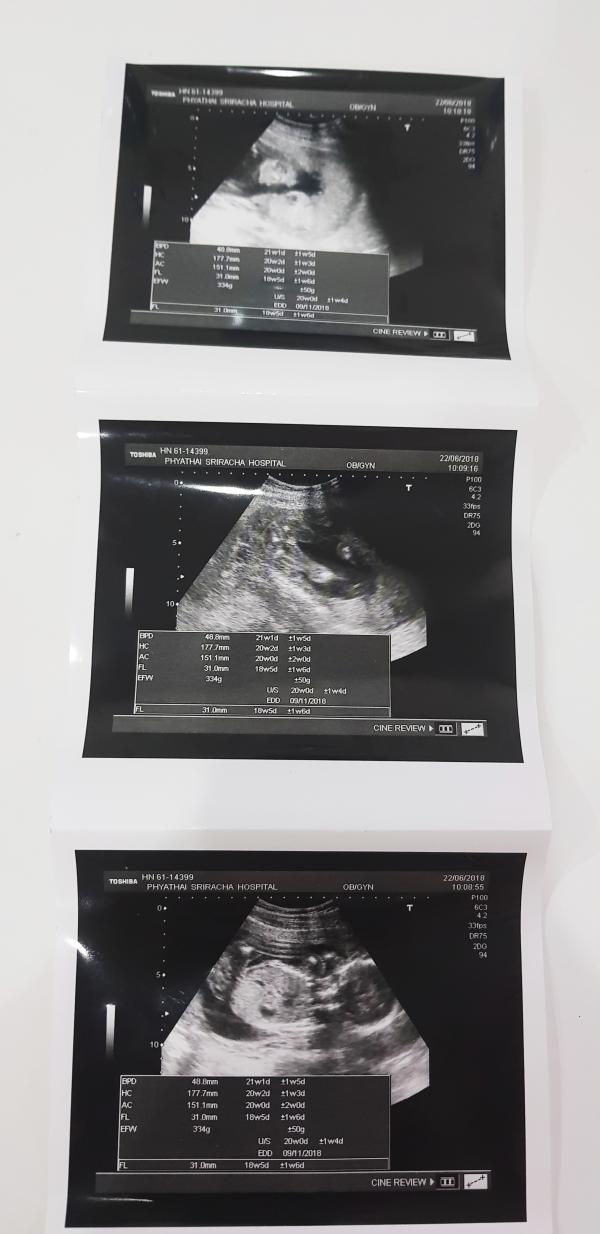

Сегодня мы были на УЗИ. 20-я неделя! Хотели , чтобы нам не говорили пол, а написали на бумажке! Но, к сожалению, ни наше терпение, ни тот факт, что многие из друзей и близких уехали, чтобы сделать сюрприз вечеринку, мы не захотели откладывать сей момент)))

В общем, все ошибались, это ДЕВОЧКА 😂💝😍 хотя мы уже и имя выбрали для пацана)))

Сегодня даже смогли немного рассмотреть ее личико, это , конечно, космическое ощущение! Она будто заглядывала к нам через прибор УЗИ , упираясь ручками в него😍 если бы эти приборы стоили дешево , мы бы каждый день смотрели 😂